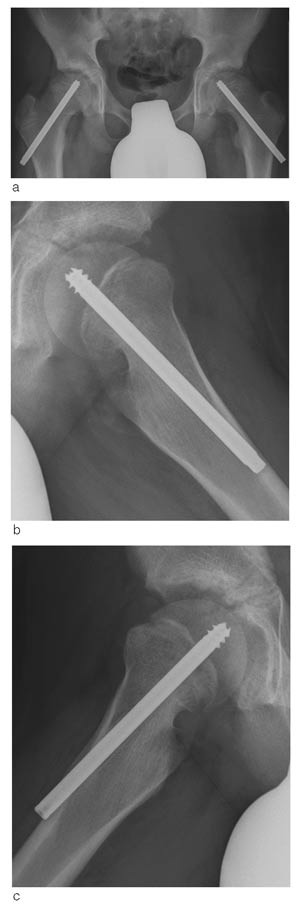

For å se på hvorvidt det skjer en fortsatt lengdevekst i collum med denne fiksasjonen, har vi målt endring i distale skrueendes protrusjon ved laterale cortex, artikulotrokantær avstand samt collumlengde ved operasjon og ved oppfølging.

Vi har målt distale skrueendes protrusjon ved laterale cortex i ti hofter. Gjennomsnittlig er den redusert med 0,53 cm per år (fig 3). Dette kan kun delvis forklares med økt bredde av femur ved økt vekst. Femurs bredde ved skruens distale ende har vi målt i seks hofter og gjennomsnittlig har femurs bredde ved laterale cortex økt med 0,17 cm per år.

Hos seks pasienter har vi målt artikulotrokantær avstand og collumlengde på frisk og affisert side ved operasjon og ved oppfølging. Den artikulotrokantære avstand er uendret på den kontralaterale friske side (2,3 cm). På affisert side har artikulotrokantær avstand gjennomsnittlig sunket med 0,5 cm (2,3 – 1,8 cm). Collumlengden har økt både på den kontralaterale friske side og på affisert side med gjennomsnittlig 0,6 cm: På affisert side i gjennomsnitt 8,9 – 9,5 cm, og på den kontralaterale friske side i gjennomsnitt 9,3 – 9,9 cm.

Vi ser at protrusjonen av distale skrueender ved den laterale cortex reduseres, og vi ser også at collumlengden øker. Dette tolker vi som tegn på at den spesialkonstruerte collumskruen tillater fortsatt vekst av collum. Hos de fleste av pasientene har feilstillingen bedret seg under behandlingen, og dette kan tyde på at den fortsatte veksten bevirker remodellering av feilstillingen. Guzzanti og medarbeidere (13) fant i sin studie fra 2004 at man oppnår fortsatt vekst av collum og remodellering av feilstilling ved bruk av en modifisert kannulert AO-skrue (kortere gjengesegment). Likeledes fant Hansson i sin studie fra 1982 (17) at en Hook-pin som er glatt over vekstskiven tillater fortsatt vekst i collum. I vårt materiale har behandling av epiphysiolysis capitis femoris med en spesialkonstruert collumskrue gitt gode resultater med lite komplikasjoner.